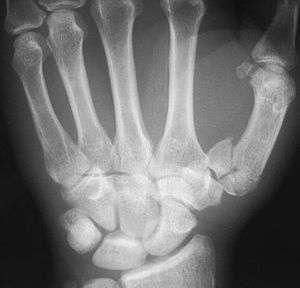

Fractures

Fractures to the first metacarpal bone account for 30-40% of all hand fractures and 25% of all metacarpal fractures (second to fractures to the fifth metacarpal bone). 80% of fractures to the first metacarpal occur at its base. [7]

Common fractures to the thumb metacarpal include Bennett's fracture and Rolando's fracture.

Fracture of the first metacarpal (Rolando's fracture).- First metacarpal bone.Deep dissection.